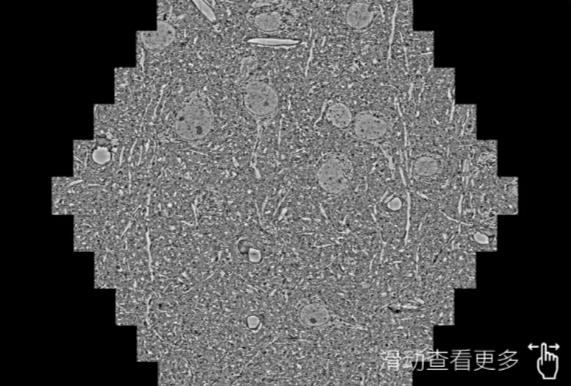

鼠脑切片。左图使用万州蔡司万州扫描电镜MultiSEM706对165μmx143pm面积区域成像,耗时仅需1.5秒。右图为鼠脑切片中30μm区域放大效果。样品由芝加哥大学B.Kasthuri提供。

使用蔡司高速万州扫描电镜MultiSEM对1mm²人脑皮层组织进行高分辨成像,并对其中的各种细胞结构进行三维重构分析。左图展示了2x3mm²组织平面中锥体神经元的三维重构效果。右图显示了局部体积神经元三维重构。图像由哈佛大学chtman实验室提供,渲染图由D. Berger 制作。